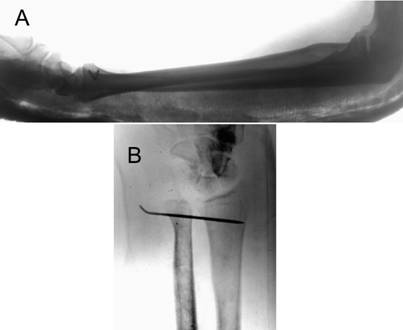

Radiographs of the forearm, including both the elbow and wrist joints, revealed an anterior dislocation of the radial head and a disruption of the DRUJ with a volar dislocation of the distal ulna [Fig.1].

Initial radiographs showing the anterion dislocation of the radial head (A, B, C) and the volar dislocation of the distal radio-ulnar joint (A, D).